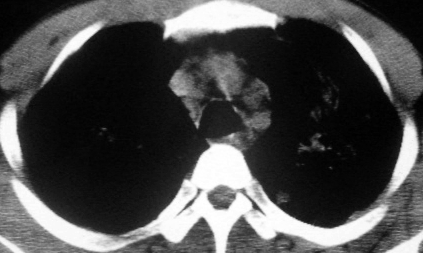

男,36岁,一月前醉酒淋雨后发热咳嗽,气短进行性加重.

抗生素治疗无效,痰检(一).

影像诊断:结核? 还有其他考虑吗?

双肺内中部见略不对称性蝶翼状高密度区,边界不清,部分呈磨玻璃样密度,并可见含气支气管征。肺门、纵隔内未见肿大淋巴结影。无胸腔积液。

考虑:1、肺炎,建议进一步查冷凝集试验除外支原体肺炎;

2、不除外霉菌感染。

双肺斑片状密度均匀病灶,边界模糊可见充气支气管征,上野多于下野,不支持结核,1肺内感染,2查肾功,中心型肺水肿待除外.

还是考虑肺水肿!蝶翼征.肺门增大,肺血管影增粗,!!病变累及中内带为主!要排外支原体感染.

支持: 双肺内中部见略不对称性蝶翼状高密度区,边界不清,部分呈磨玻璃样密度,并可见含气支气管征。肺门、纵隔内未见肿大淋巴结影。无胸腔积液。